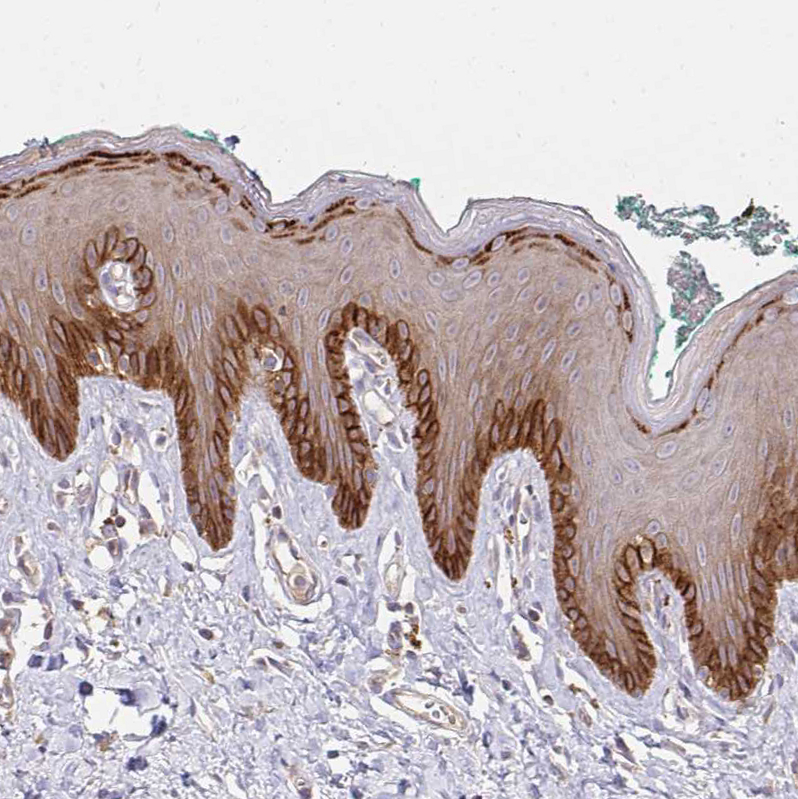

Immunohistochemical staining of human endometrium, rectum, skin and urinary bladder using Anti-ITGA2 antibody HPA060991 (A) shows similar protein distribution across tissues to independent antibody HPA063556 (B).